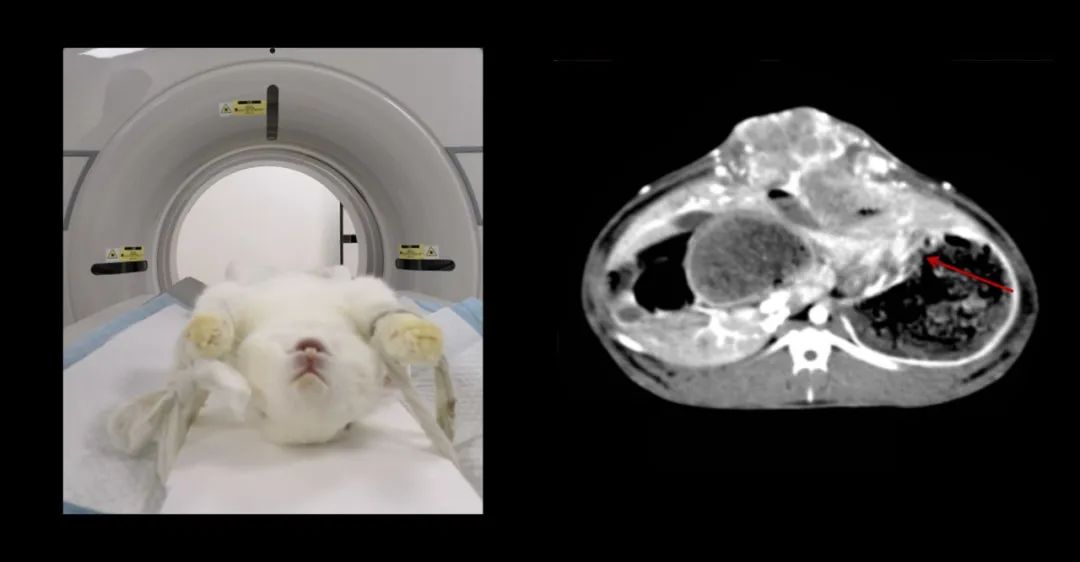

7歲,38kg的金毛狗近期總是嘔吐,CT全身平掃+增強,發(fā)現肝和胃占位性病變。

640 (2).jpg